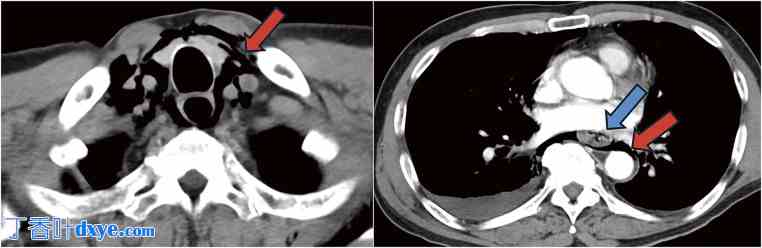

增强CT扫描显示咽部、颈部和纵隔均有气肿,食管下段壁增厚并断裂,右侧胸腔积液,以及气胸(图1)。为了减压和引流,在食管内插入了胃管。对于轻微渗漏,胃管保留在原位进行保守治疗。通过胃管持续注射造影剂显示,造影剂从食管下段右侧渗漏至纵隔(图2),从而证实了自发性食管破裂。因此,进行了急诊手术。由于怀疑穿孔位于食管下段右侧,因此选择了腹腔镜手术。

图1. 计算机断层扫描(CT)。CT显示从咽部到食管胃交界处(红色箭头)的纵隔积气。蓝色箭头显示食管壁增厚和破裂。